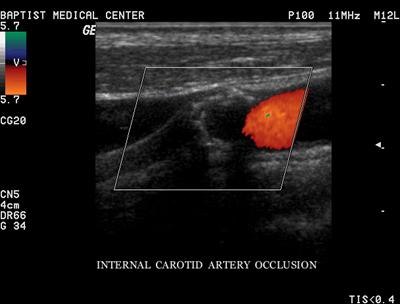

Occlusion

Complete blockage

- Best used with the terms probable & total

- Complete filling of the vessel internal area with heterogeneous material

- No blood flow

What must one do in calling an occlusion

sensitize the equipment before doing so

Decrease PRF

Increase color gain, use power Doppler